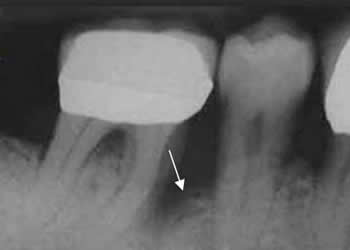

Fig 37. Enfermedad endodental.

Rx periapical. Se identifica caries. (Flecha gruesa). Extensión periapical de la infección, con disminución de la densidad del hueso que rodea las raíces. (Flechas delgadas).